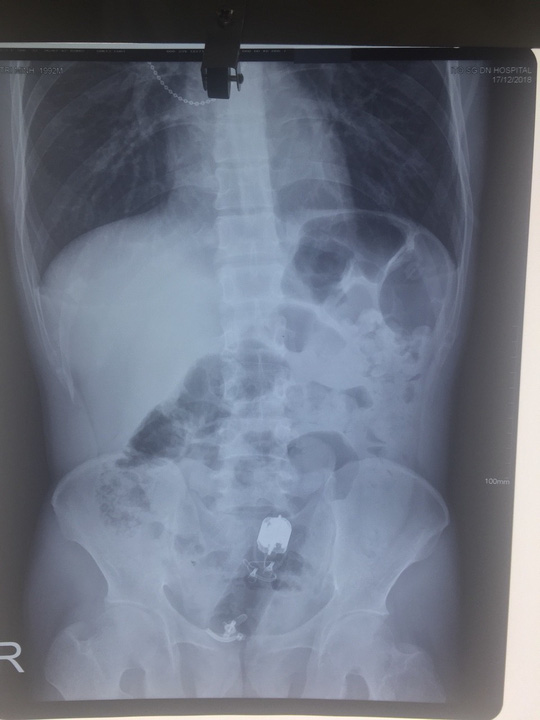

Dương vật giả chui sâu vào trực tràng thanh niên - hình ảnh sau khi chụp X Quang cho thấy. Ảnh: NLĐ.

Qua X-quang và nội soi, các bác sĩ phát hiện dị vật đã chui sâu vào trong trực tràng của người đàn ông đến 10cm và rất khó lấy ra. Dị vật là dương vật giả dài đến 18 cm.